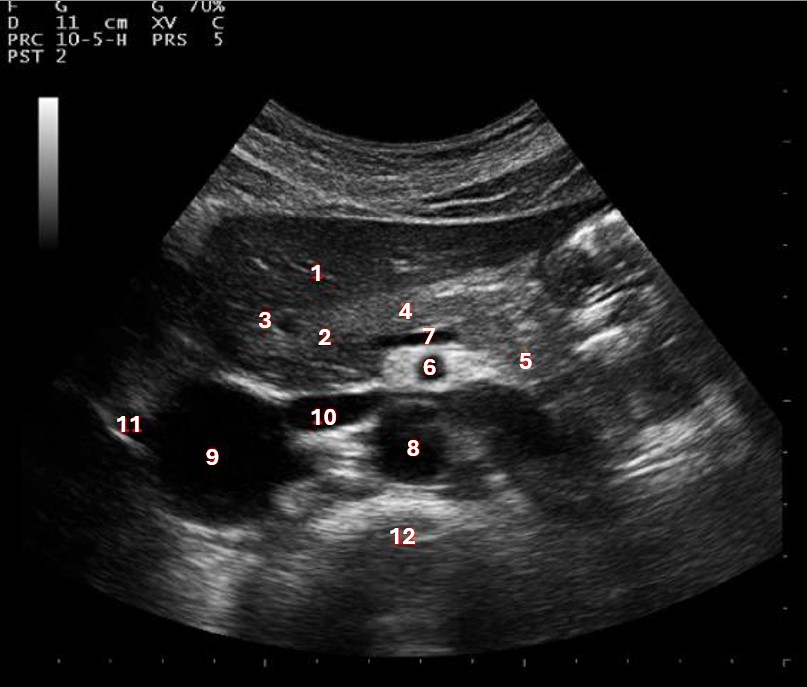

Which of the following structures is labeled number #1?

Left hepatic vein

What lobe of the liver is indicated by #1?

Posterior right lobe

Which of the following structures is labeled #2?

Middle hepatic vein

Which of the numbered vessels is part of the portal system?

2

Which of the following structures is labeled #3?

IVC

Which of the following structures is labeled #6?

Medial left lobe

What structures last vessel is indicated by #4?

Which of the following structures is labeled #4?

Right hepatic vein

Which of the following structures is labeled #8?

What structure/vessel is indicated by #12?

Spine

What structure/vessel is indicated by #3?

Lateral branch of LPV

What structure/vessel is indicated by #7?

Splenic vein